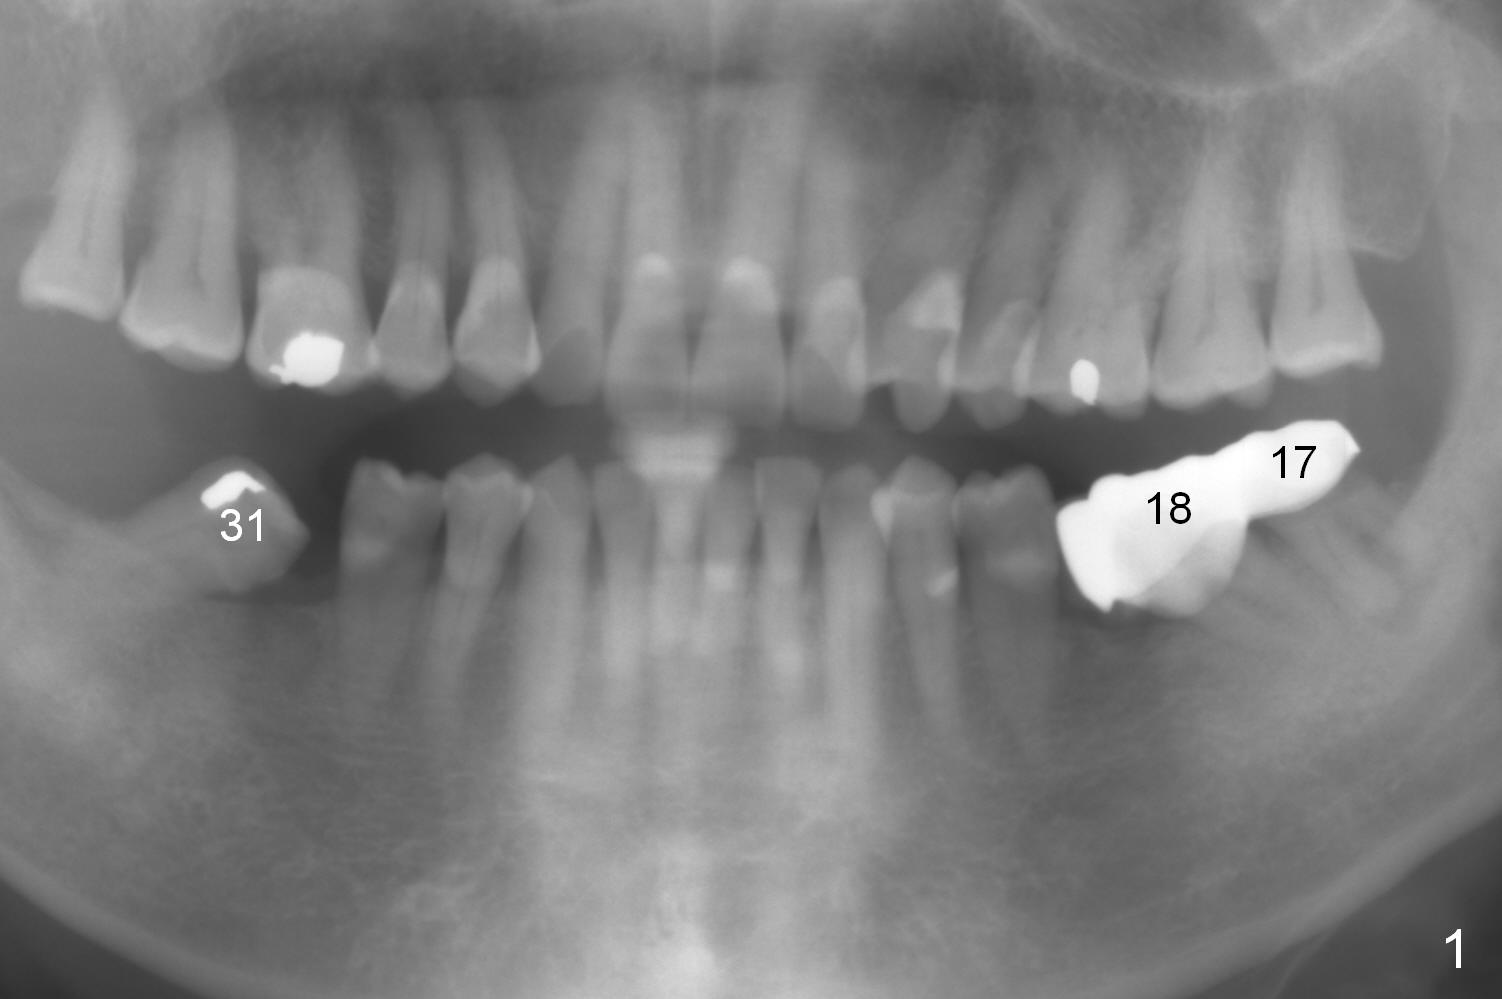

A 82-year-old man has pain in the lower left bridge. There is a buccal apical fistula associated with the tooth #17 (Fig.1). An immediate implant will be placed at #17 after bridge removal (Fig.2,3 blue). Once it osteointegrates, it will be used an anchorage (direct (instead of indirect), most efficient) to upright the tooth #18 (change the longitudinal axis from red line to purple one (Fig.4); white circle: center of resistance (rotation)). Then an implant will be placed at #19 (white rectangle).

Take Alginate impression and keep it moist. It will be used as a stent for temporization later on. After the tooth #17 is extracted with Clindamycin treatment, a FC dummy implant (5x9 mm) will be placed, followed by 6x4(2) mm abutment (Fig.3,4 pink). If there is severe vertical height issue, change to Magicore. Due to schedule conflict, prepare UF for this case instead.